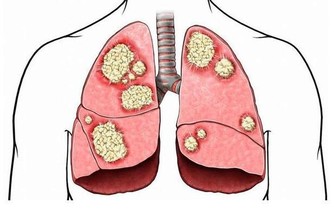

早上剛睡醒頭痛,痛一個固定的地方並且每天都痛,還合併有一些症狀,

比如說講話有問題、手腳有麻木情形有可能腦部有問題,或是咳嗽、打噴嚏、彎腰時頭痛會加劇,

有這些症狀的時候就要注意了,因為這有可能是腦部腫瘤所引起的。